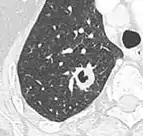

A "notch sign".[9]

- Margin morphology: a spiculated margin is a risk factor for cancer.[8] Benign causes tend to have a well defined border, whereas lobulated lesions or those with an irregular margin extending into the neighbouring tissue tend to be malignant.[10] In particular, spiculations are highly predictive of malignancy with a positive predictive value up to 90%.[9] Also, a "notch sign", which is an abrupt indentation of the nodule, increases the risk of cancer, but may also be found in granulomatous diseases.[9]